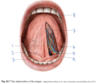

What structures serve as the posterior boundary of the oral cavity?

Sulcus terminalis (#4)

Palatoglossal arches (#5)

Which structure is labeled by #4?

Levator palati

Which structure is labeled by #8?

Apex of the tongue

Which structure is labeled by #6?

Eustachian tube

(Also #9)

Which structures are labeled by #6?

Deep lingual artery and vein